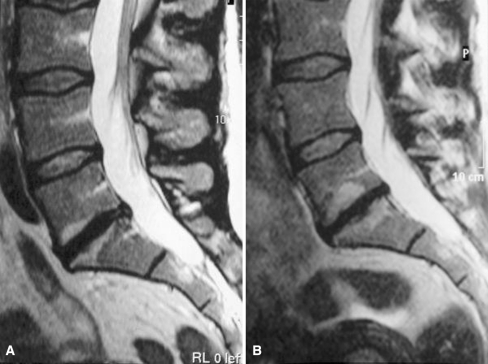

Fig. 1.

a On T2-weighted image (T2WI) at baseline, a subchondral hyperintensity (M1) adjacent to both endplates of L5/S1 disc space and a focal hypointense lesion subchondrally adjacent to the lower endplate. Disc signal intensity slightly decreased at L4/5, decreased at L3/4 and strongly decreased at L5/S1. Disc height decreased at L5/S1. b After follow-up the focal hypointense lesion and the surrounding subchondral hyperintensity adjacent to the lower endplate have enlarged as well as the hyperintensity adjacent to the upper endplate and a new focal lesion has appeared subchondrally in its center. Disc height at L5/S1 is strongly decreased (further)